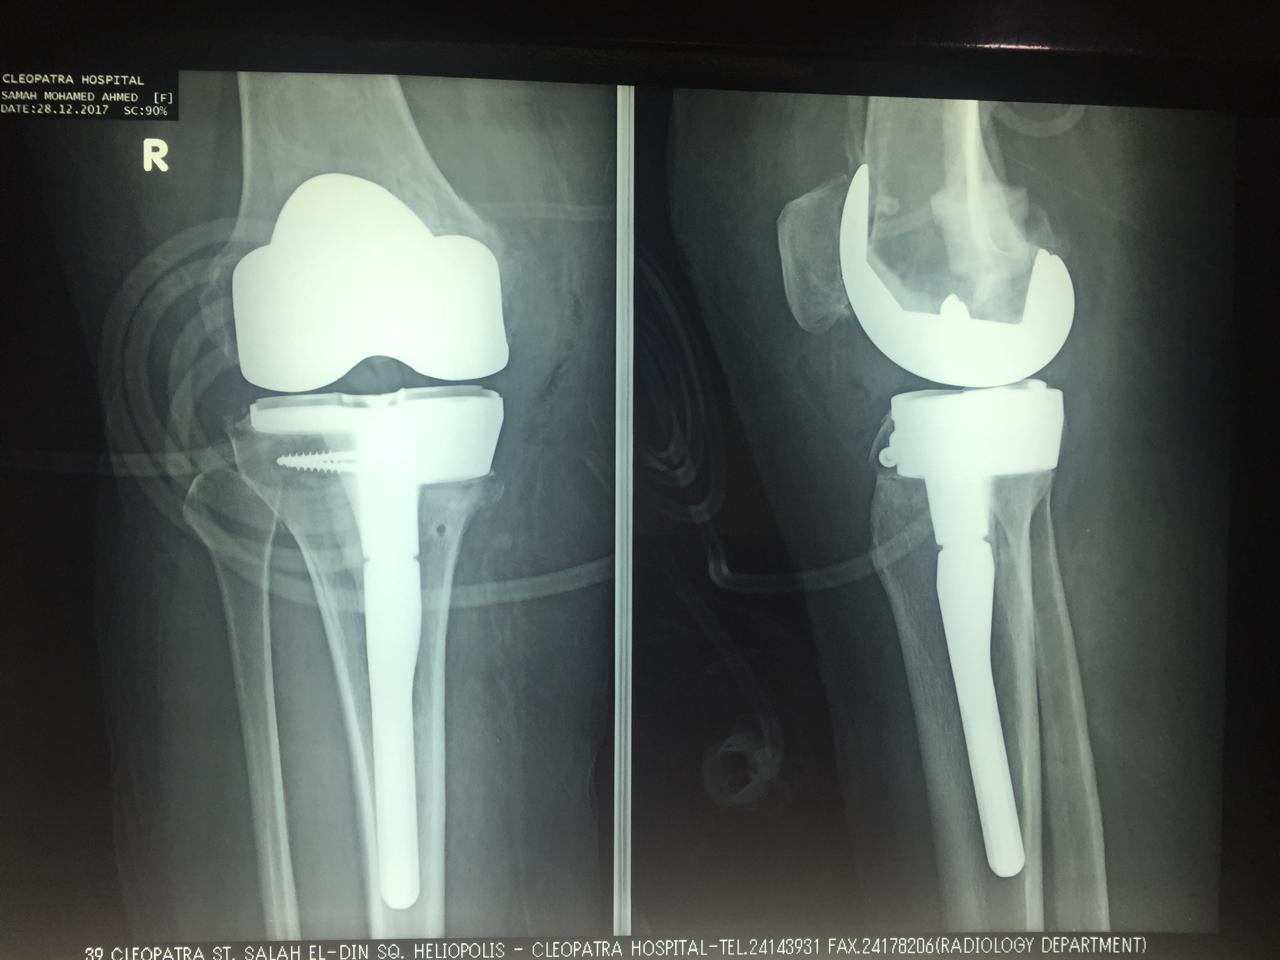

تم تركيب مفصل ذو مواصفات خاصه لتعويض عجز العظام بالركبة.